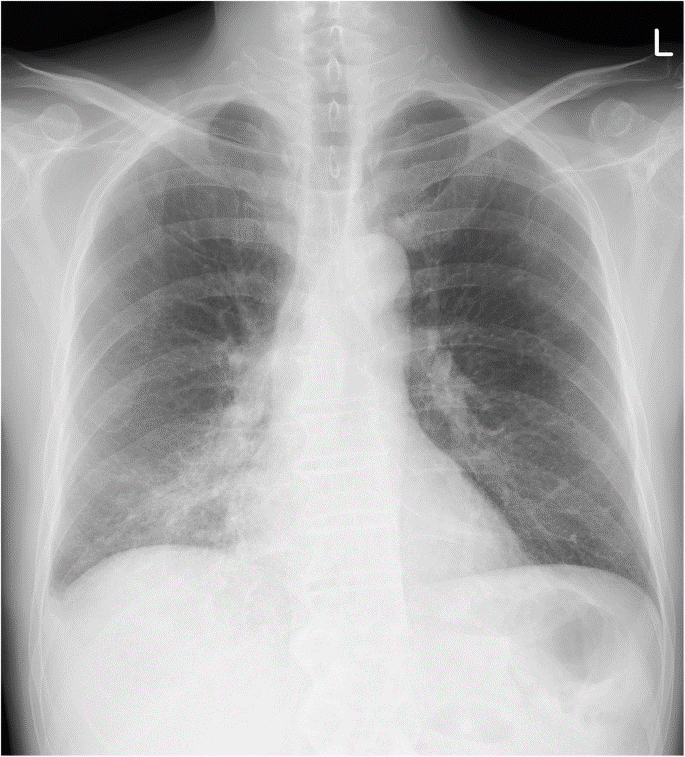

Hình ảnh tổn thương phổi do nhiễm vi khuẩn Legionella

Bệnh nhiễm khuẩn Legionella do vi khuẩn gây ra, bệnh thường lây lan ở những khu vực có nước tù đọng, hoặc thiếu nguồn nước sạch. Nhiễm khuẩn Legionella dẫn đến khó thở và có thể gây viêm phổi.